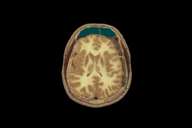

LAI used The Visible Human Project to show a subdural hematoma and surgical drainage procedure.